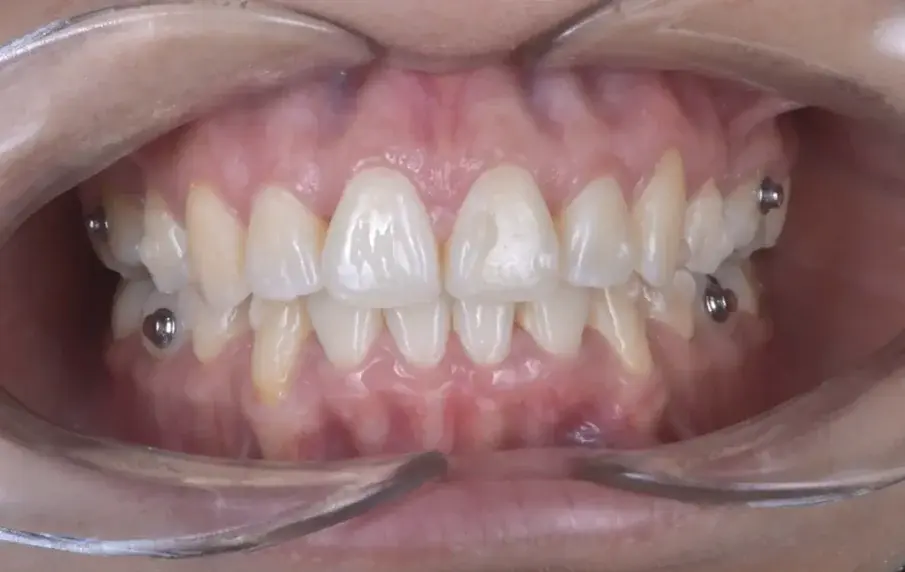

Преди началото на лечението с алайнери, вторите премолари на горната и долната челюст бяха екстрахирани, за да се създаде пространство. При ортодонтско лечение се постига дистализация на предните зъби чрез използване на максимално мандибуларно закрепване и умерено максиларно закрепване (фиг. 5–7).

С ортодонтското лечение беше постигната дистализация на предните зъби чрез използване на максимална опора на долната челюст и умерена на горната челюст (фиг. 5–7). В края на лечението беше постигната стабилна двустранна оклузия от клас I, както и нормално наклоняване и ретрузия на предните зъби, което доведе до подобряване на профила (фиг. 8–10).

Фиг. 7а: Окончателни интраорални снимки.

Фиг. 7b: Окончателни интраорални снимки.

Фиг. 7c: Окончателни интраорални снимки.

Фиг. 7d: Окончателни интраорални снимки.